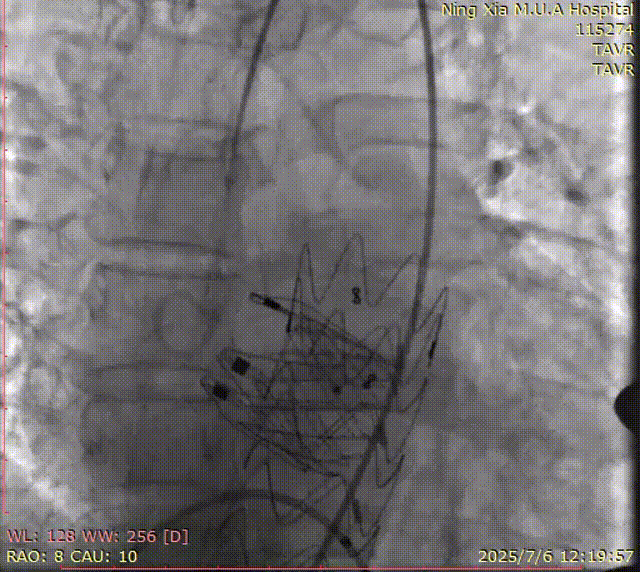

术中回顾及效果

手术过程顺利。术中通过右窦居中造影、定位件入窦造影及释放后功能确认等关键步骤,确保瓣膜锚定准确。器械时间约10分钟。术中超声检查未见瓣周漏,瓣膜位置及功能评估良好,整个过程衔接紧密,无术中并发事件发生。术后即刻超声复查提示人工生物瓣启闭良好,平均跨瓣压差为6mmHg,血流速度正常。患者恢复情况稳定,心功能显著改善。

夹持件顺利入窦

术后造影